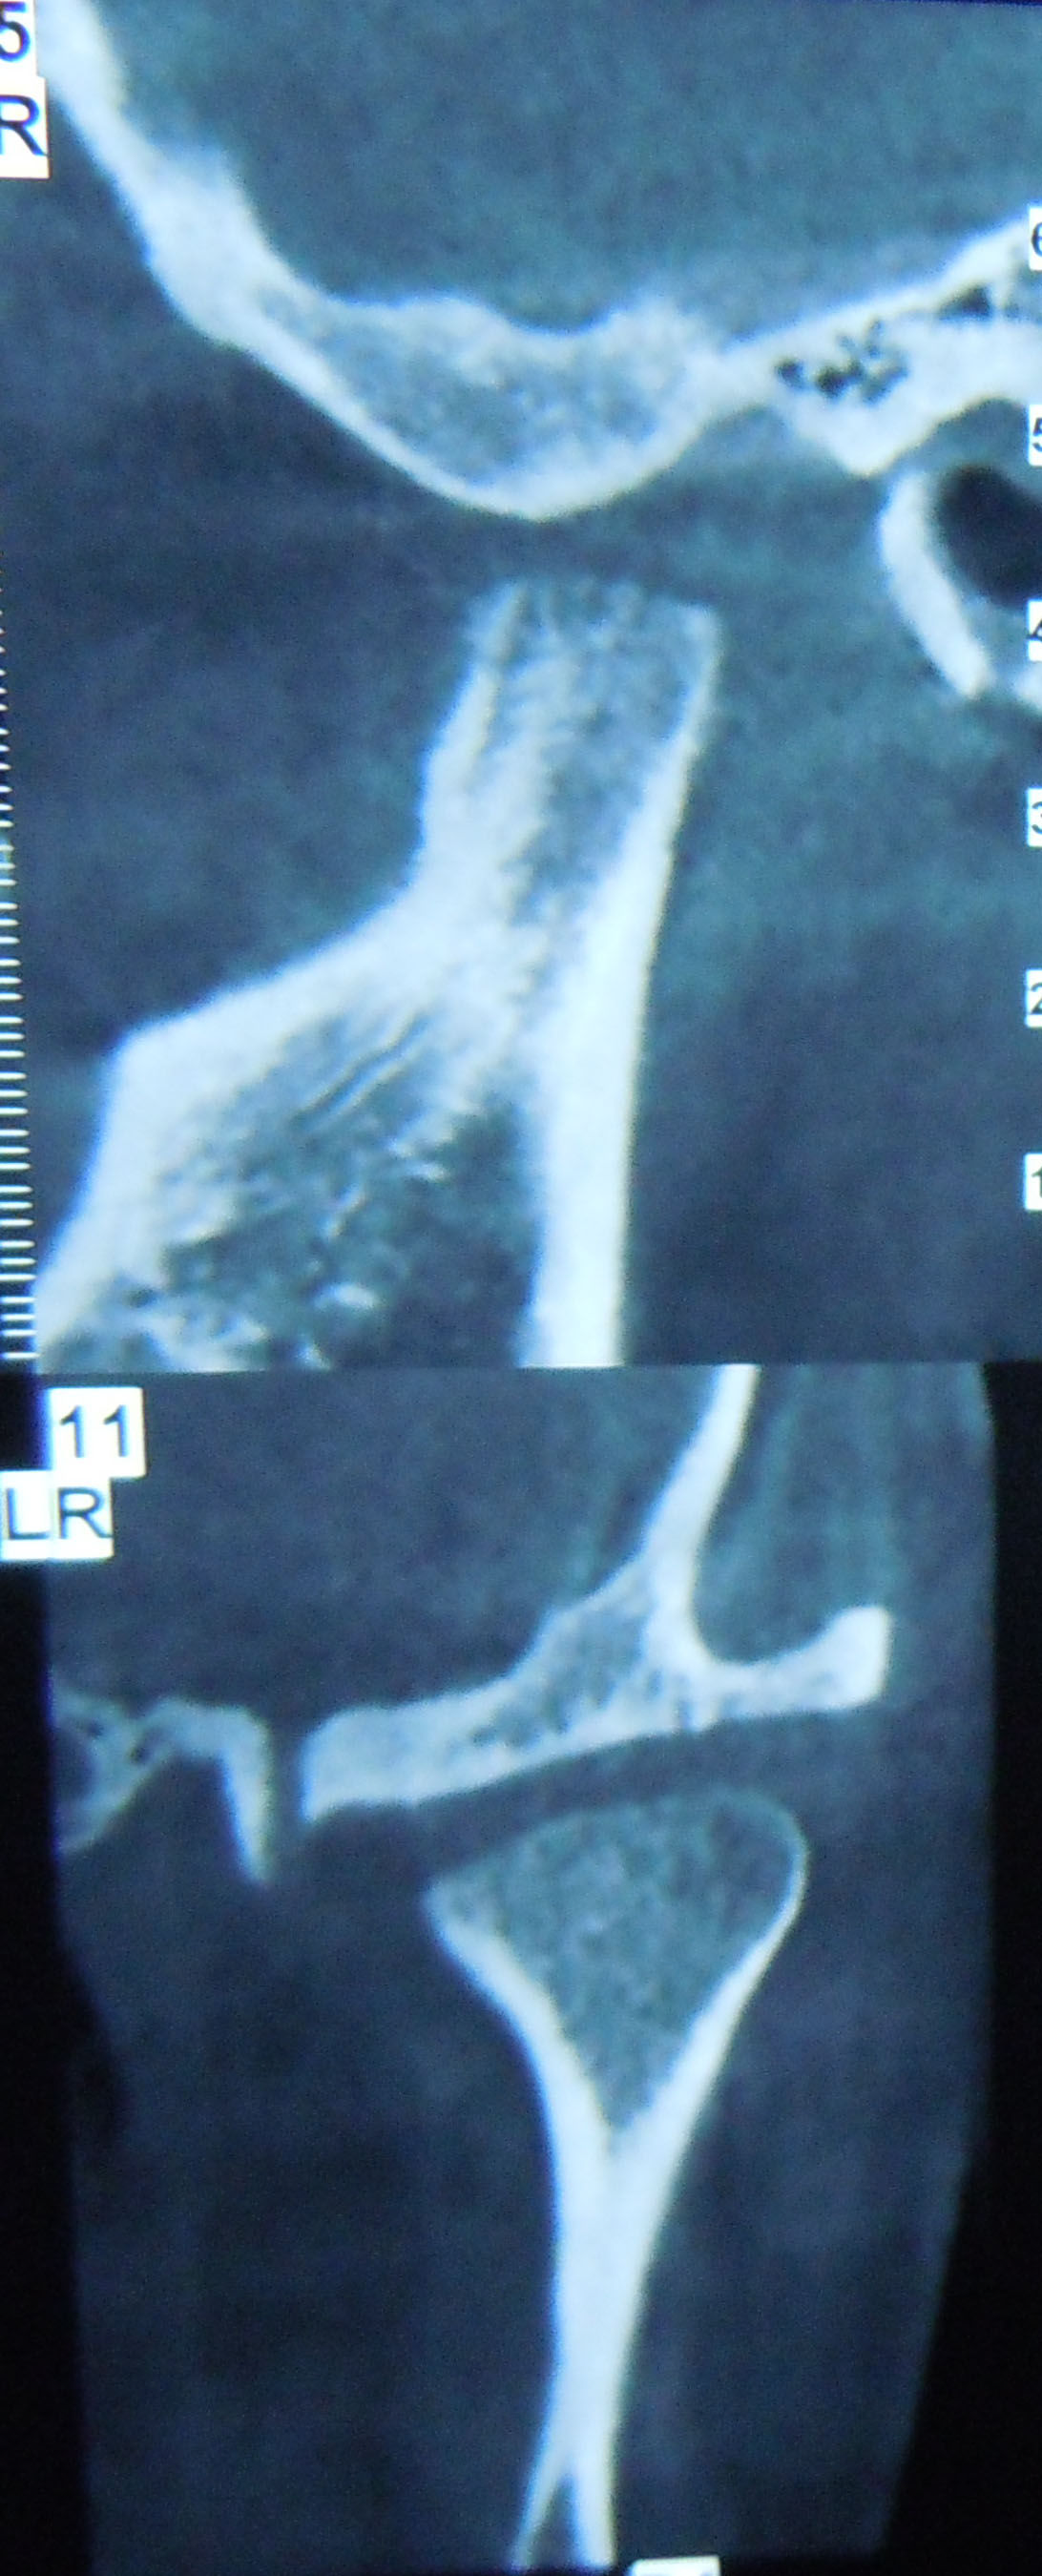

关节长期的脱臼,手法是不可能复位的,因为软组织已经充满的关节窝,关节窝内已经没有髁突的位置了。所以在手术中,我们切除关节结节和一部分髁突,这样也不能在术后复位髁突,所以我又在上下颌打上牵引钉,把下颌拉会关节窝。

要求拍CT,ct显示左侧髁突骨质改建良好,可以考虑正畸治疗这种反颌,后来我们考虑这个人都27岁了,对面容要求也不高了,而且牵引钉拉髁突向后的力量不足,是因为上下颌牙尖的锁结很厉害,所以建议戴薄稳定合垫,打开咬合,同时戴颏兜加大向后的力量,再观察一个月。

一个月时髁突的骨质改建得很好,对于这种长期陈旧性的关节脱位,用手术复位也不容易,就别提什么手法了。关节复位的方法理论上很多,但是实际关节脱位超过3天,我就没有见过不手术能复位的。